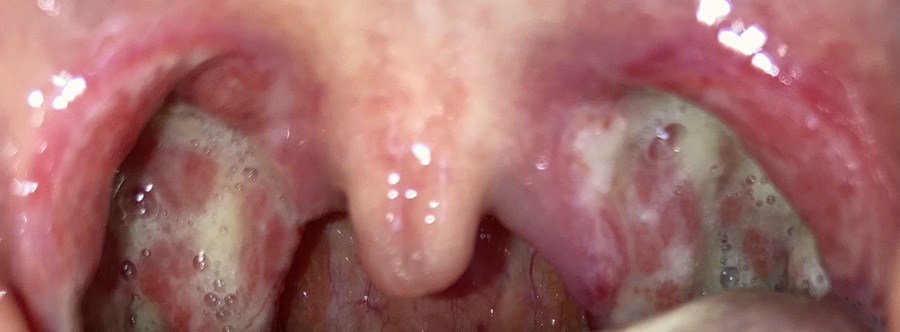

이건 수술 후 사진을 찍은 거야.

점점 피부가 보이기 시작한다.하지만 역시 아픔은 가시지 않는다.